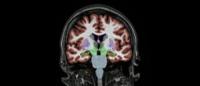

CREB3L2-ATF4 pairs (red) inside different neurons. Image from Hengst laboratory / Columbia University.